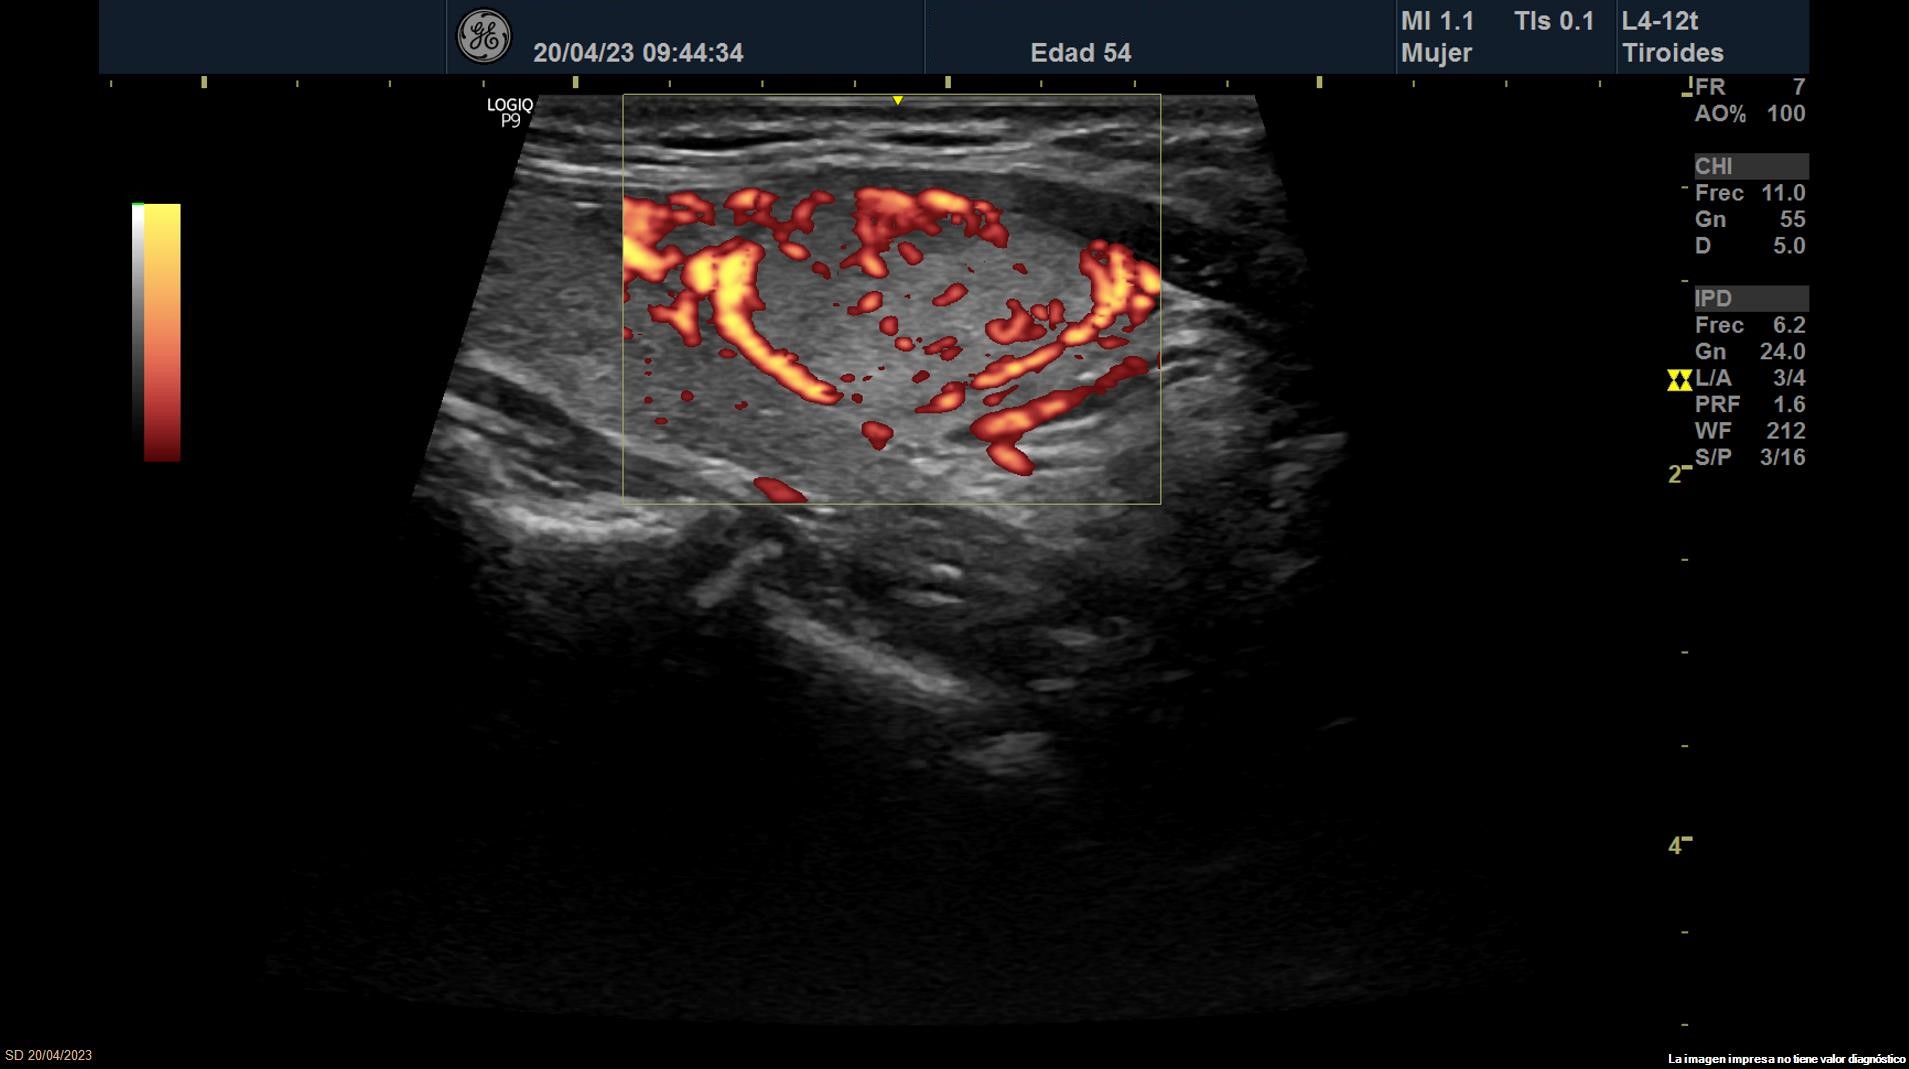

Se objetiva una adenopatía de 0,8 cm de aspecto benigno, ovalada y con bordes definidos. Además, se realiza ecografía tiroidea:

Ante los hallazgos obtenidos, nos planteamos el diagnostico diferencial entre los nódulos tiroideos benignos y malignos. Se deriva a Endocrinología donde realizan nueva ecografía que concuerda con la nuestra.